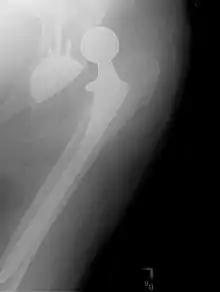

![]() صورة بالأشعة السينية تظهر الورك الأيسر (يمين الصورة) الذي تم استبداله بآخر اصطناعي. صورة بالأشعة السينية تظهر الورك الأيسر (يمين الصورة) الذي تم استبداله بآخر اصطناعي. | |

يتم بعد الجراحة، إجراء تصوير الشعاعي لمنطقة المفصل المزروع وذلك للتأكد من نجاح العملية وضمان التكوين المناسب للأطراف الاصطناعية للورك. يؤثر اتجاه تجويف الحق المزروع على نطاق حركة الساق، كما يعد أيضا عاملا محددا لإمكانية حدوث خطر الخلع من عدمه.[31] لهذا الغرض، يتم اللجوء لإجراء قياسات خاصة لمقارنتها بالقيم الطبيعية. من بين أهم هذه القياسات نجد مثلا ميلان الحق ودرجة إنقلابه إلى الأمام بالنسبة للمستوى الإكليلي والمستوى السهمي على التوالي.